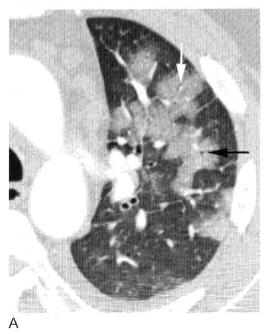

图2 实变:边界不清的,毛玻璃样致密影伴“肺泡充气征”

A. 放大影像细节观察右肺下叶实变呈磨玻璃样边界不清的致密影,内含有小圆形透亮影,称为肺泡充气征,尽管与实际肺泡大小并不相符;B. 右下叶肺炎患者胸部CT显示边界不清的磨玻璃样实变(白色箭头),实变区内小的局灶性透亮影(黑色箭头)为“肺泡充气征”。

3. 肺泡充气征

如果肺实变不融合,可以看到间杂小的局灶性透亮区,代表未受累的肺组织(图2),这些透亮区被称为“肺泡充气征”,但因为肺泡太小无法在X线片上看到,这是一个误称。这些透亮区反映了不完全肺实变。